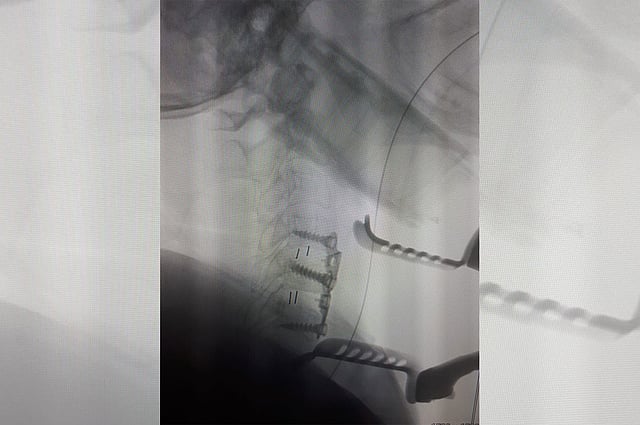

وتعرضت المريضة، إلى تنمل تسبب في عدم قدرتها على استعمال أطرافها بشكل طبيعي، وبعد إجراء كافة الفحوصات المخبرية والإشعاعية تبين وجود انزلاقين غضروفيين بين الفقرات الرابعة والخامسة، والخامسة والسادسة.

وقرر الطبيب المعالج إجراء تدخل اجراحي، بعملية تضمنت دمج وتثبيت الفقرات بواسطة دعامات وشرائح وتكللت بالنجاح؛ حيث عادت المريضة للتحكم بالأطراف المتضررة، وغادرت بعد ذلك المستشفى وهي بصحة جيدة.